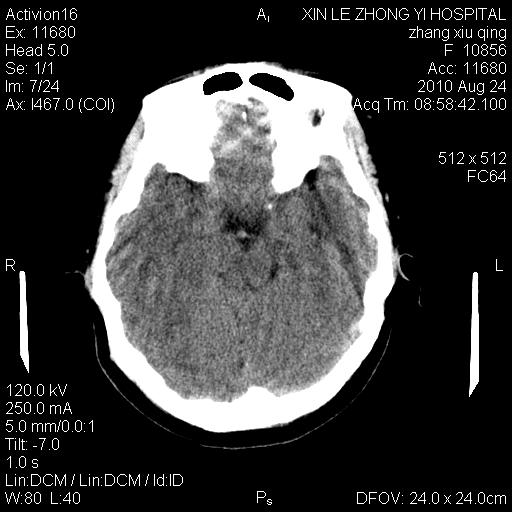

标题: CT28569:看看鞍上池正常吗 [打印本页]

标题: CT28569:看看鞍上池正常吗

女 24 偶有头晕

怎么这么多伪影?我感觉没什么特别异常哦,是不是伪影所至呀

病史?感觉有水肿,炎症或转移

伪影多,建议行mri!

建议薄层扫描或mr

没什么!只是扫描层面与听眦线不平行